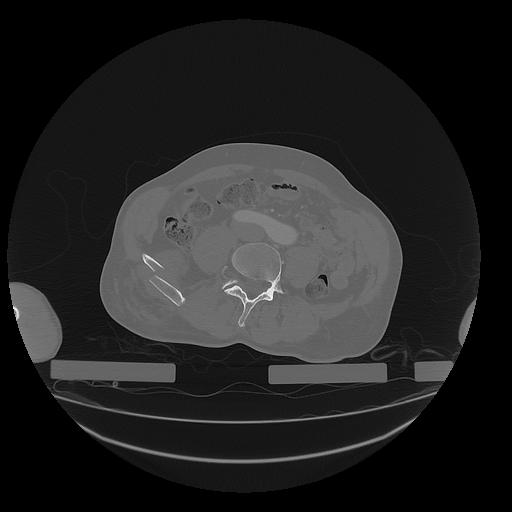

31 PULMON,CE,Vol,1.0,PULMON,,